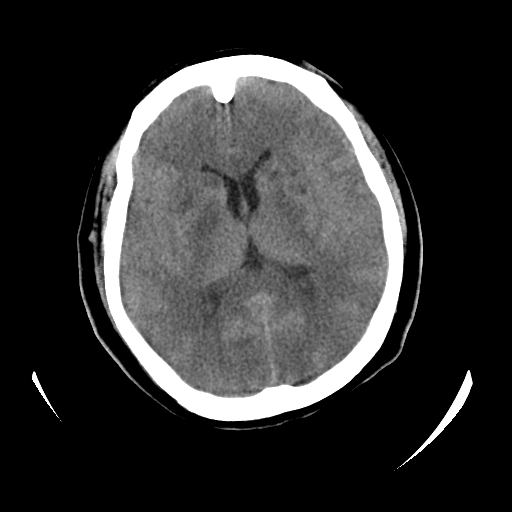

女,53岁,发现昏迷1天,血压不高,有精神病史。临床诊断:脑梗死?

ct诊断:1、双侧基底节区对称性脑梗塞。

2、双侧额叶、枕叶广泛密度减低,考虑缺血梗塞可能性大。

3、脑池小,脑沟浅,提示颅内高压。

测左枕叶白质ct值 约22hu 。请各位老师给出恬当诊断。

征象:病变呈对称性分布于双侧大脑半球,累及范围广泛,白质较灰质密度减低更为明显;脑沟变浅,脑池变窄;